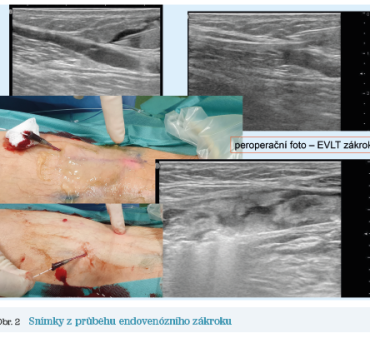

Obr. 2 Snímky z průběhu endovenózního zákrokuPrvním příkladem je muž narozený v roce 1963, který měl symptomatické retikulární varikozity dorzální strany bérce. Na základě pouhého klinického vyšetření by se mohlo zdát, že udávané potíže v podobě bolesti, tíže, intermitentních perimaleolárních otoků nejsou primárně vyvolány žilní nedostatečností. Nález by byl dle klasifikace CEAP hodnocen jako C1‑2 Ep As Pr. Po podrobném mappingu povrchového žilního systému však byla diagnostikována insuficience SPJ, odkud byl reflux distribuován do VSP, zde dosahoval až k laterálnímu kotníku. Se SPJ komunikovala též vena fossa poplitea, která proximálně probíhala souběžně s VSP a v proximální třetině bérce opustila svůj kompartment a rozpadla se ve více epifasciálních přítoků, v jejichž rámci se pak též tvořily retikulární varikozity. Jako další zdroj refluxu byl diagnostikován insuficientní perforátor v rámci extensio cranialis, které ve fossa poplitea ústilo do VSP a podílelo se na progresi její insuficience (obr. 1). Navíc v rámci doplňkového pletysmografického testu (venous reflux testing, VRT) byl diagnostikován reflux ve svalových žilách bérce s kapilárním návratem (capillary refill time, CRT) 5 sekund, což je známka významně snížené funkce svalově‑žilní pumpy. Díky tomuto nálezu byl nález dle klasifikace CEAP vyhodnocen jako C1,2s,3 Ep As,d,p Pr. Takovýto nález jednoznačně splňuje podmínky pro indikaci intervenčního řešení.

Obr. 3 Pooperační nález, kde jsou vidět obliterované kmenové žílyDaný jedinec se rozhodl pro řešení pomocí endovenózního zákroku. Snímky z jeho realizace ukazuje obrázek 2, pooperační nález pak obrázek 3.